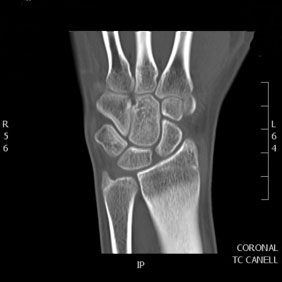

Tomografía computarizada Osteoarticular

< Volver a "Tomografía Computarizada (TC) con Inteligencia artificial"Con esta prueba valoraremos la patología de las vertebras, fracturas, hernias, protusiones discales, …

No requiere de ninguna preparación previa, y el tiempo de exploración no suele sobrepasar los 10 minutos